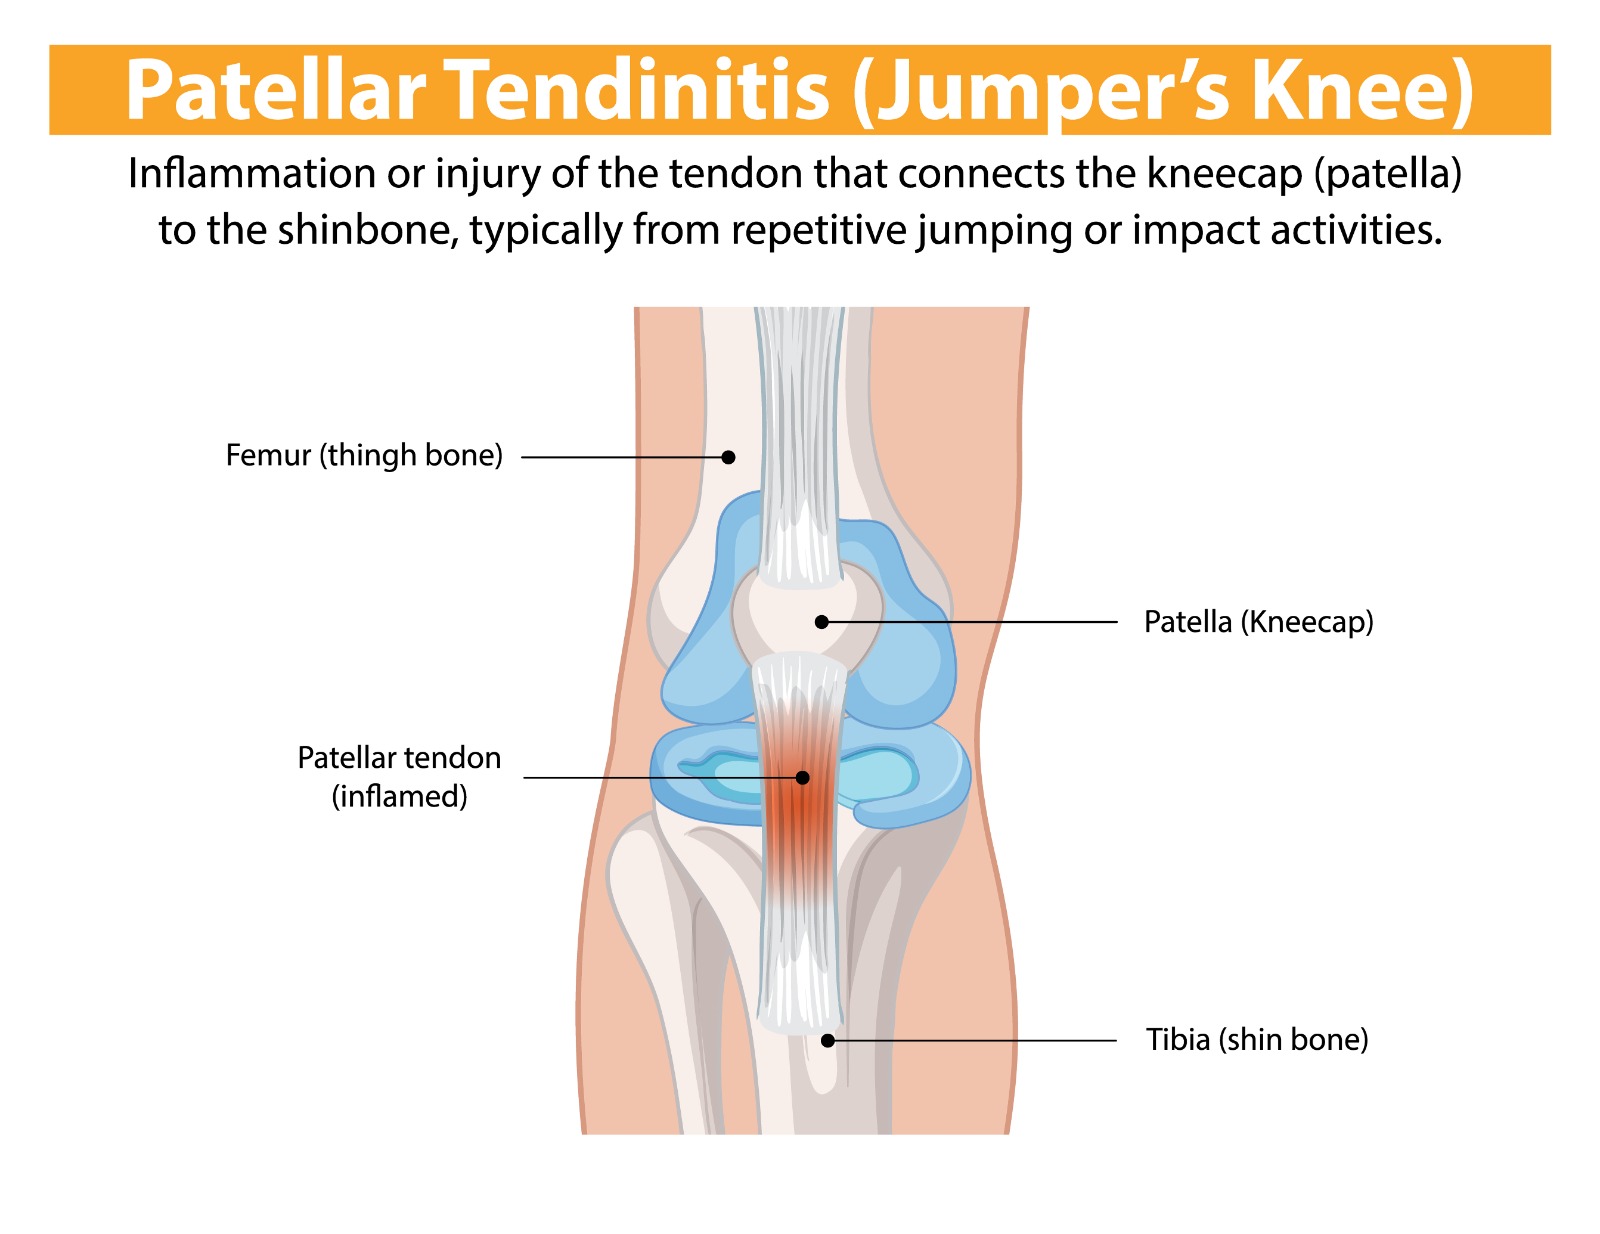

Patellar tendinopathy — commonly known as ‘jumper’s knee’ — is an overuse condition affecting the patellar tendon, which connects the kneecap (patella) to the shinbone (tibia). It is caused by repetitive loading of the tendon beyond its capacity to recover, leading to tendon degeneration, pain, and functional impairment. It is particularly prevalent in jumping athletes — volleyball and basketball players, high jumpers, and footballers — and is one of the most challenging sports injuries to manage due to the tendon’s poor healing response.

- Anterior knee pain localised to the inferior pole of the patella (just below the kneecap)

- Tenderness on pressing the inferior patellar tendon